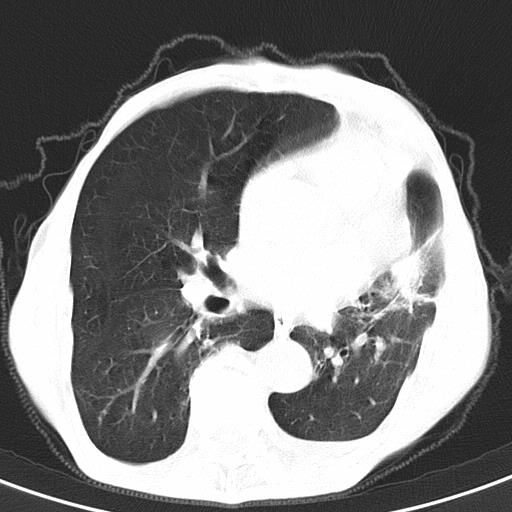

患者78岁,咳嗽胸闷一年余,近月来左侧胸痛;

患者左侧胸廓塌陷说明是长期病变,考虑tb性胸膜炎可能性大,另外有明显的肺气肿,建议行结核菌素实验,或者增强扫描

1.慢支肺气肿。2.左肺感染,建议治疗后复查。3.左侧少量胸水。

1.慢支肺气肿。2.左肺感染,建议治疗后复查,待除外继发性肺结核合并感染。3.左侧少量胸水。

1)考虑左肺慢性感染性病变(结核可能)。2)左肺上叶周围型肺癌不排除;建议追踪复查。3)肺气肿。4)左侧胸腔积液,左侧胸膜增厚、粘连。